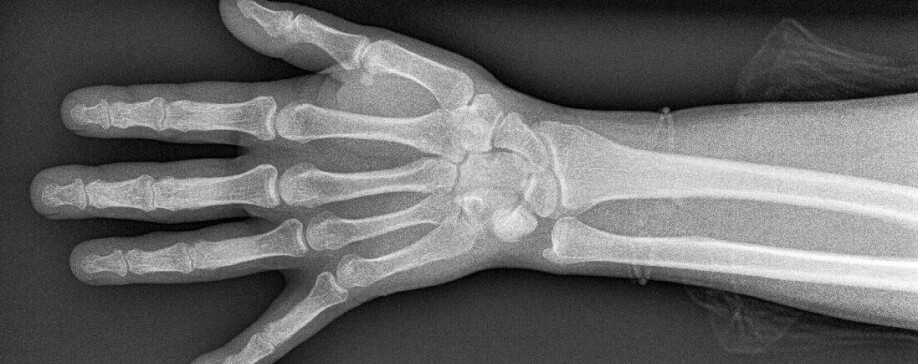

Rheumatoid arthritis is an autoimmune disease in which a person’s immune system attacks their own tissue. RA causes a lot of swelling, pain and stiffness in the joints. In addition, the disease increases the risk of cardiovascular disease, osteoporosis and inflammation of the blood vessels. People with RA thus have a shorter life expectancy.